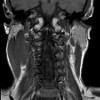

MRI of the soft tissues of the neck.

МРТ мягких тканей шеи. Метод сканирования шеи в постоянном магнитном поле с серией цифровых изображений и генерацией трехмерного изображения. Он используется для диагностики воспалительных и опухолевых процессов в органах и тканях шеи, при подозрении на травматическое повреждение и при наличии неметаллических инородных тел в гортани и трахее. Исследование проводится для выявления врожденных аномалий развития. Кисты могут быть необходимы для подготовки к операции на органах шеи. МРТ реже используется для оценки распространенности патологических процессов в щитовидной железе. Обследование является нативным или высококонтрастным, что особенно важно при диагностике опухолей. Процедура неинвазивная, проводится амбулаторно и в стационаре.